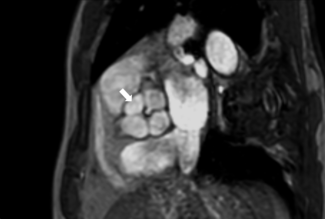

A 78-year-old woman with a background of hypertension and osteoarthritis presented with a history of syncope secondary to severe aortic stenosis. She underwent a computed tomography (CT) scan that showed a heavily calcific trileaflet aortic...